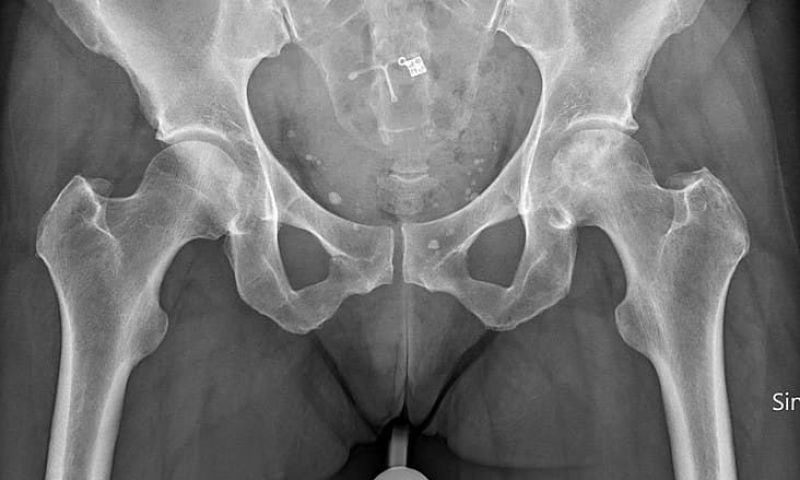

Avascular necrosis is a degenerative bone condition. It is a disease that is a result of the short term or permanent loss of blood supply to the bone. The lack of blood supply to the bone can lead to tiny breaks in the bone which can cause the bone to collapse. The condition is also known as osteonecrosis. If avascular necrosis occurs near a joint, the joint surface may in turn collapse. The most common sites of avascular necrosis are the femoral head, knee, talus, and humeral head. The hip is the most common site of avascular necrosis.